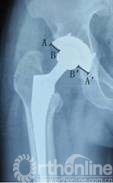

7例术前发现假体周围炎性假瘤患者,均进行聚乙烯磨损和线性磨损率测量。聚乙烯磨损表现在骨盆正位X线片上为聚乙烯内衬不对称(图2),两侧差值为股骨头偏移距离。本组病例股骨头偏移距离为2.00mm~7.12mm,平均3.57mm。

图2 X线片上AB=A’B’,表示聚乙烯无磨损,如果AB≠A’B’,则表示内外侧股骨头不对称,存在聚乙烯磨损